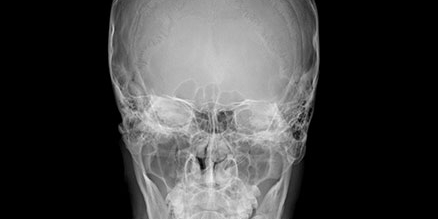

Light guided free FOV

Less is Better

Low Dose

Just scan the only area where you need. Minimize x-ray radiation dose.